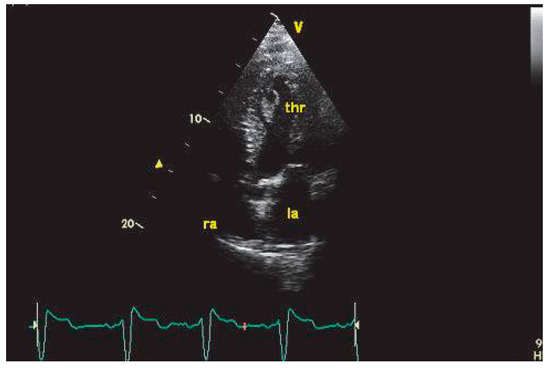

This report describes a case of involvement of inferior vena cava and the right atrium (RA) by a hepatocellular carcinoma (HCC), incidentally discovered during a transthoracic echocardiography in a patient with segmental left ventricular dysfunction,...